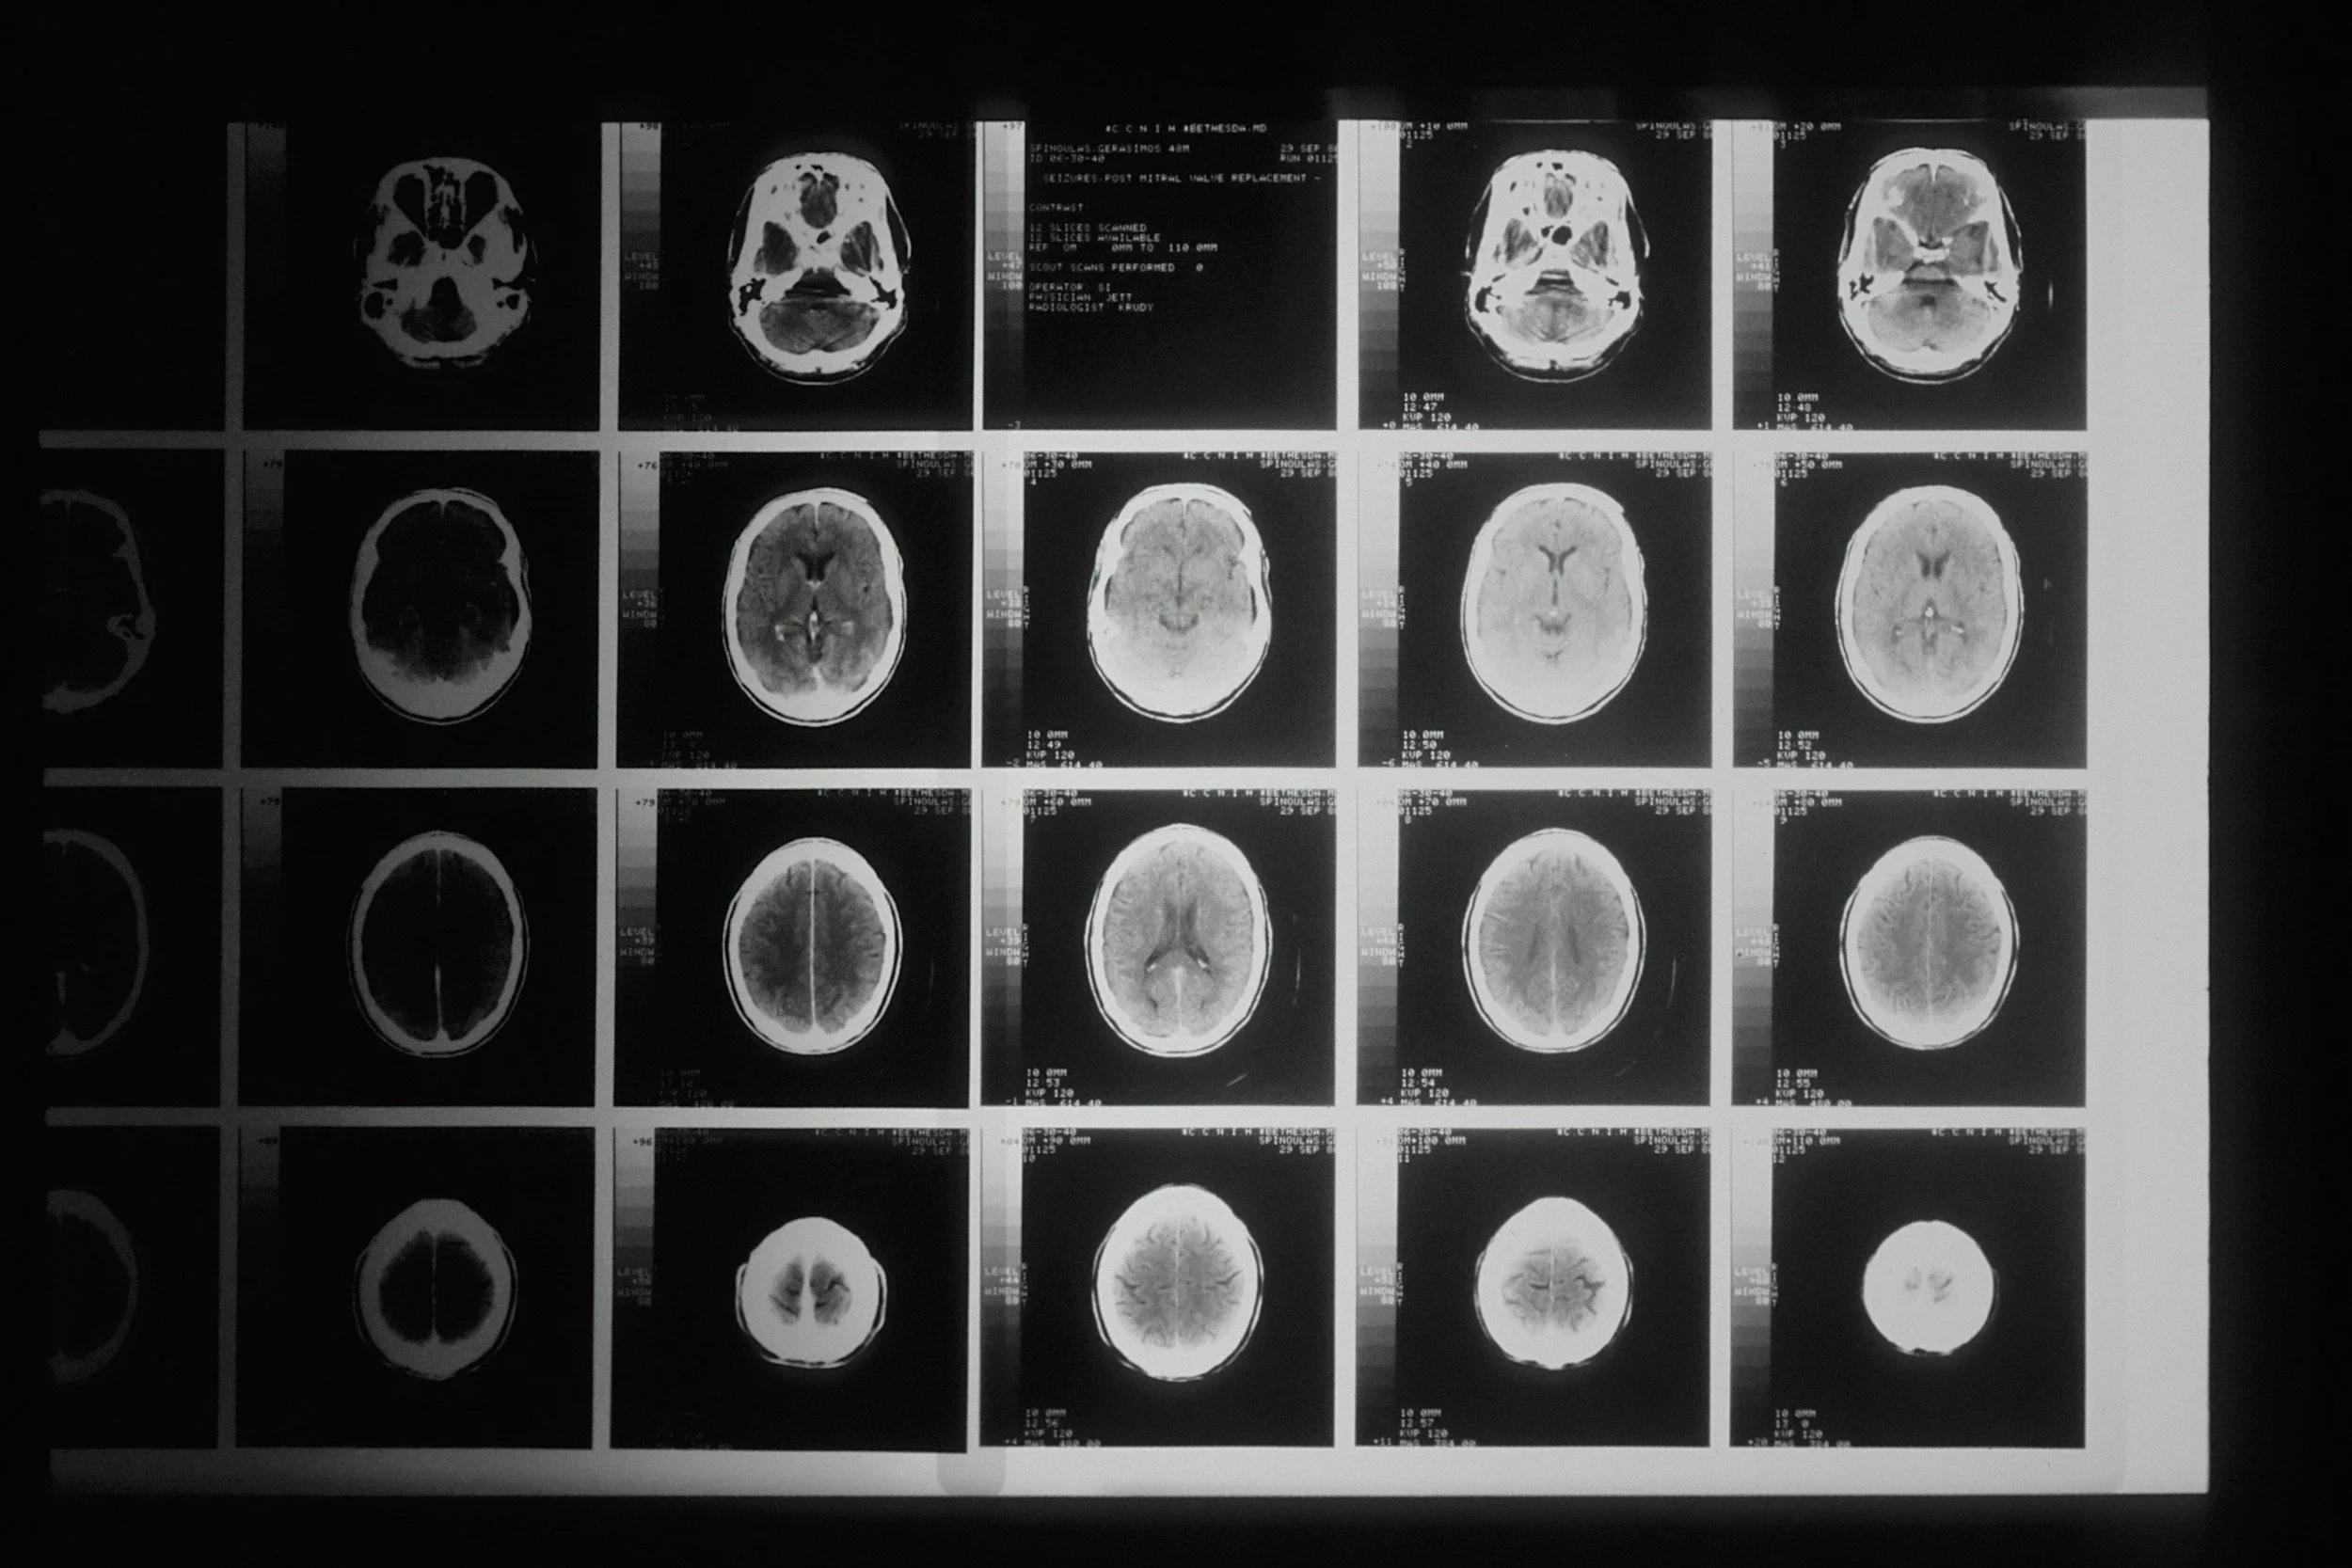

Alzheimer’s is one of the biggest medical and social challenges of our generation...but we’ve done little to address it.

Dementia Blur explores the relationship between people living with Alzheimer’s disease and their caregivers. This film follows two women and their mothers as they share their story of trials, sacrifice and love as this treacherous disease progresses.